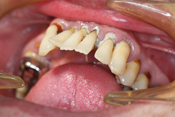

WORST TEETH Pictures from Warren Dentistry

This can happen to your teeth when proper Dental Hygiene is not practiced.

Patient 1